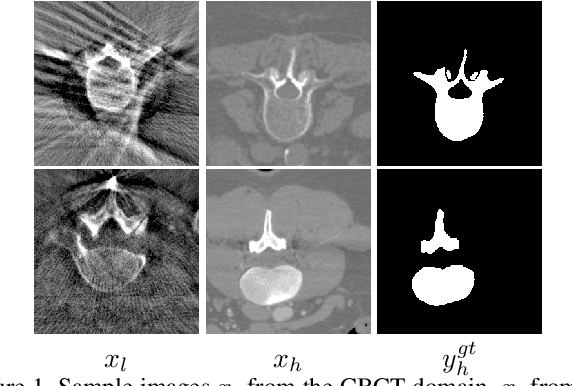

We investigate the unsupervised learning of the vertebra segmentation, artifact reduction and modality translation of CBCT images. To this end, we formulate this problem under a unified framework that jointly addresses these three tasks and intensively leverages the knowledge sharing. The unsupervised learning of this framework is enabled by 1) a novel shape-aware artifact disentanglement network that supports different forms of image synthesis and vertebra segmentation and 2) a deliberate fusion of knowledge from an independent CT dataset. Specifically, the proposed framework takes a random pair of CBCT and CT images as the input, and manipulates the synthesis and segmentation via different combinations of the decodings of the disentangled latent codes. Then, by discovering various forms of consistencies between the synthesized images and segmented , the learning is achieved via self-learning from the given CBCT and CT images obviating the need for the paired (i.e., anatomically identical) groundtruth data. Extensive experiments on clinical CBCT and CT datasets show that the proposed approach performs significantly better than other state-of-the-art unsupervised methods trained independently for each task and, remarkably, the proposed approach achieves a dice coefficient of 0.879 for unsupervised CBCT vertebra segmentation.